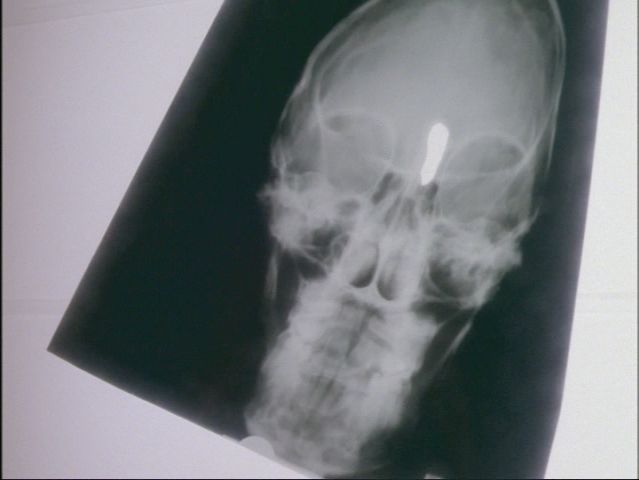

Scully egy röntgenfelvételt mutat Muldernek, amely

tisztán mutatja, hogy Dana testében, a homloküreg és az agy között,

rákos daganat terjed. Műtétileg nem eltávolítható és ha tovább

növekszik, akkor Scullynak nem sok esélye marad a túlélésre.